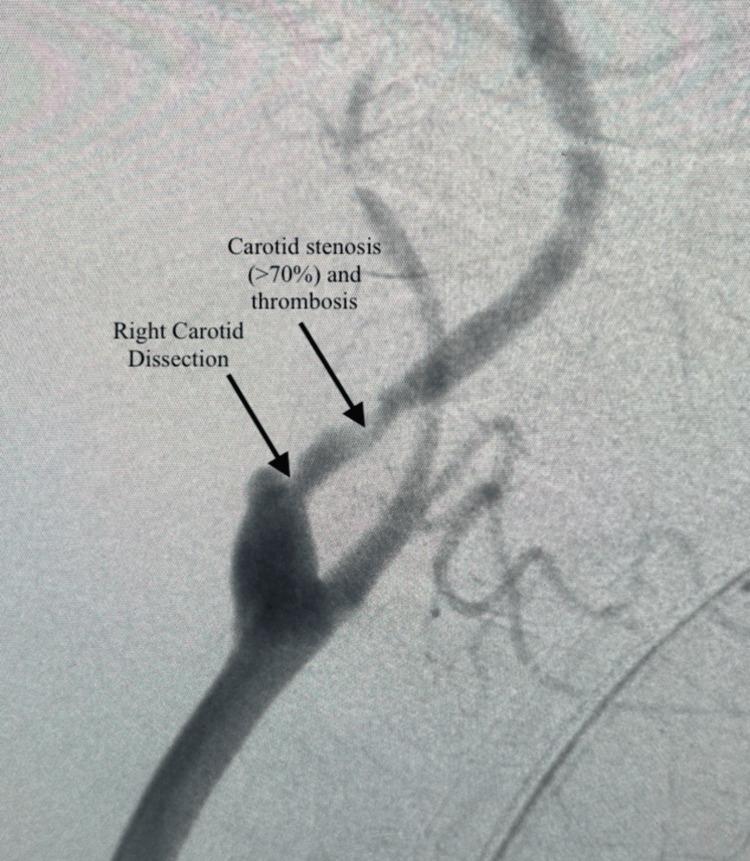

Carotid artery dissection (CAD) is a condition that compromises blood flow and leads to serious complications such as a stroke or cerebrovascular accident (CVA). This case report demonstrates an unusual case of right internal carotid artery dissection, stenosis of >70%, and an intraluminal thrombus. The patient presented to the emergency department with complaints of right-sided neck pain and severe headache status-post a complicated pregnancy. A computed tomography (CT) angiogram of the right carotid was conducted and showed a right internal carotid artery dissection with 70% luminal stenosis and thrombosis. Carotid endarterectomy (CEA), transfemoral carotid angioplasty with stenting (CAS), or transcarotid artery revascularization (TCAR) were all surgical intervention options that were explored. Risks and benefits were compared between the three surgical intervention options, and transcarotid artery revascularization was deemed the best surgical option in this patient's case.

摘要